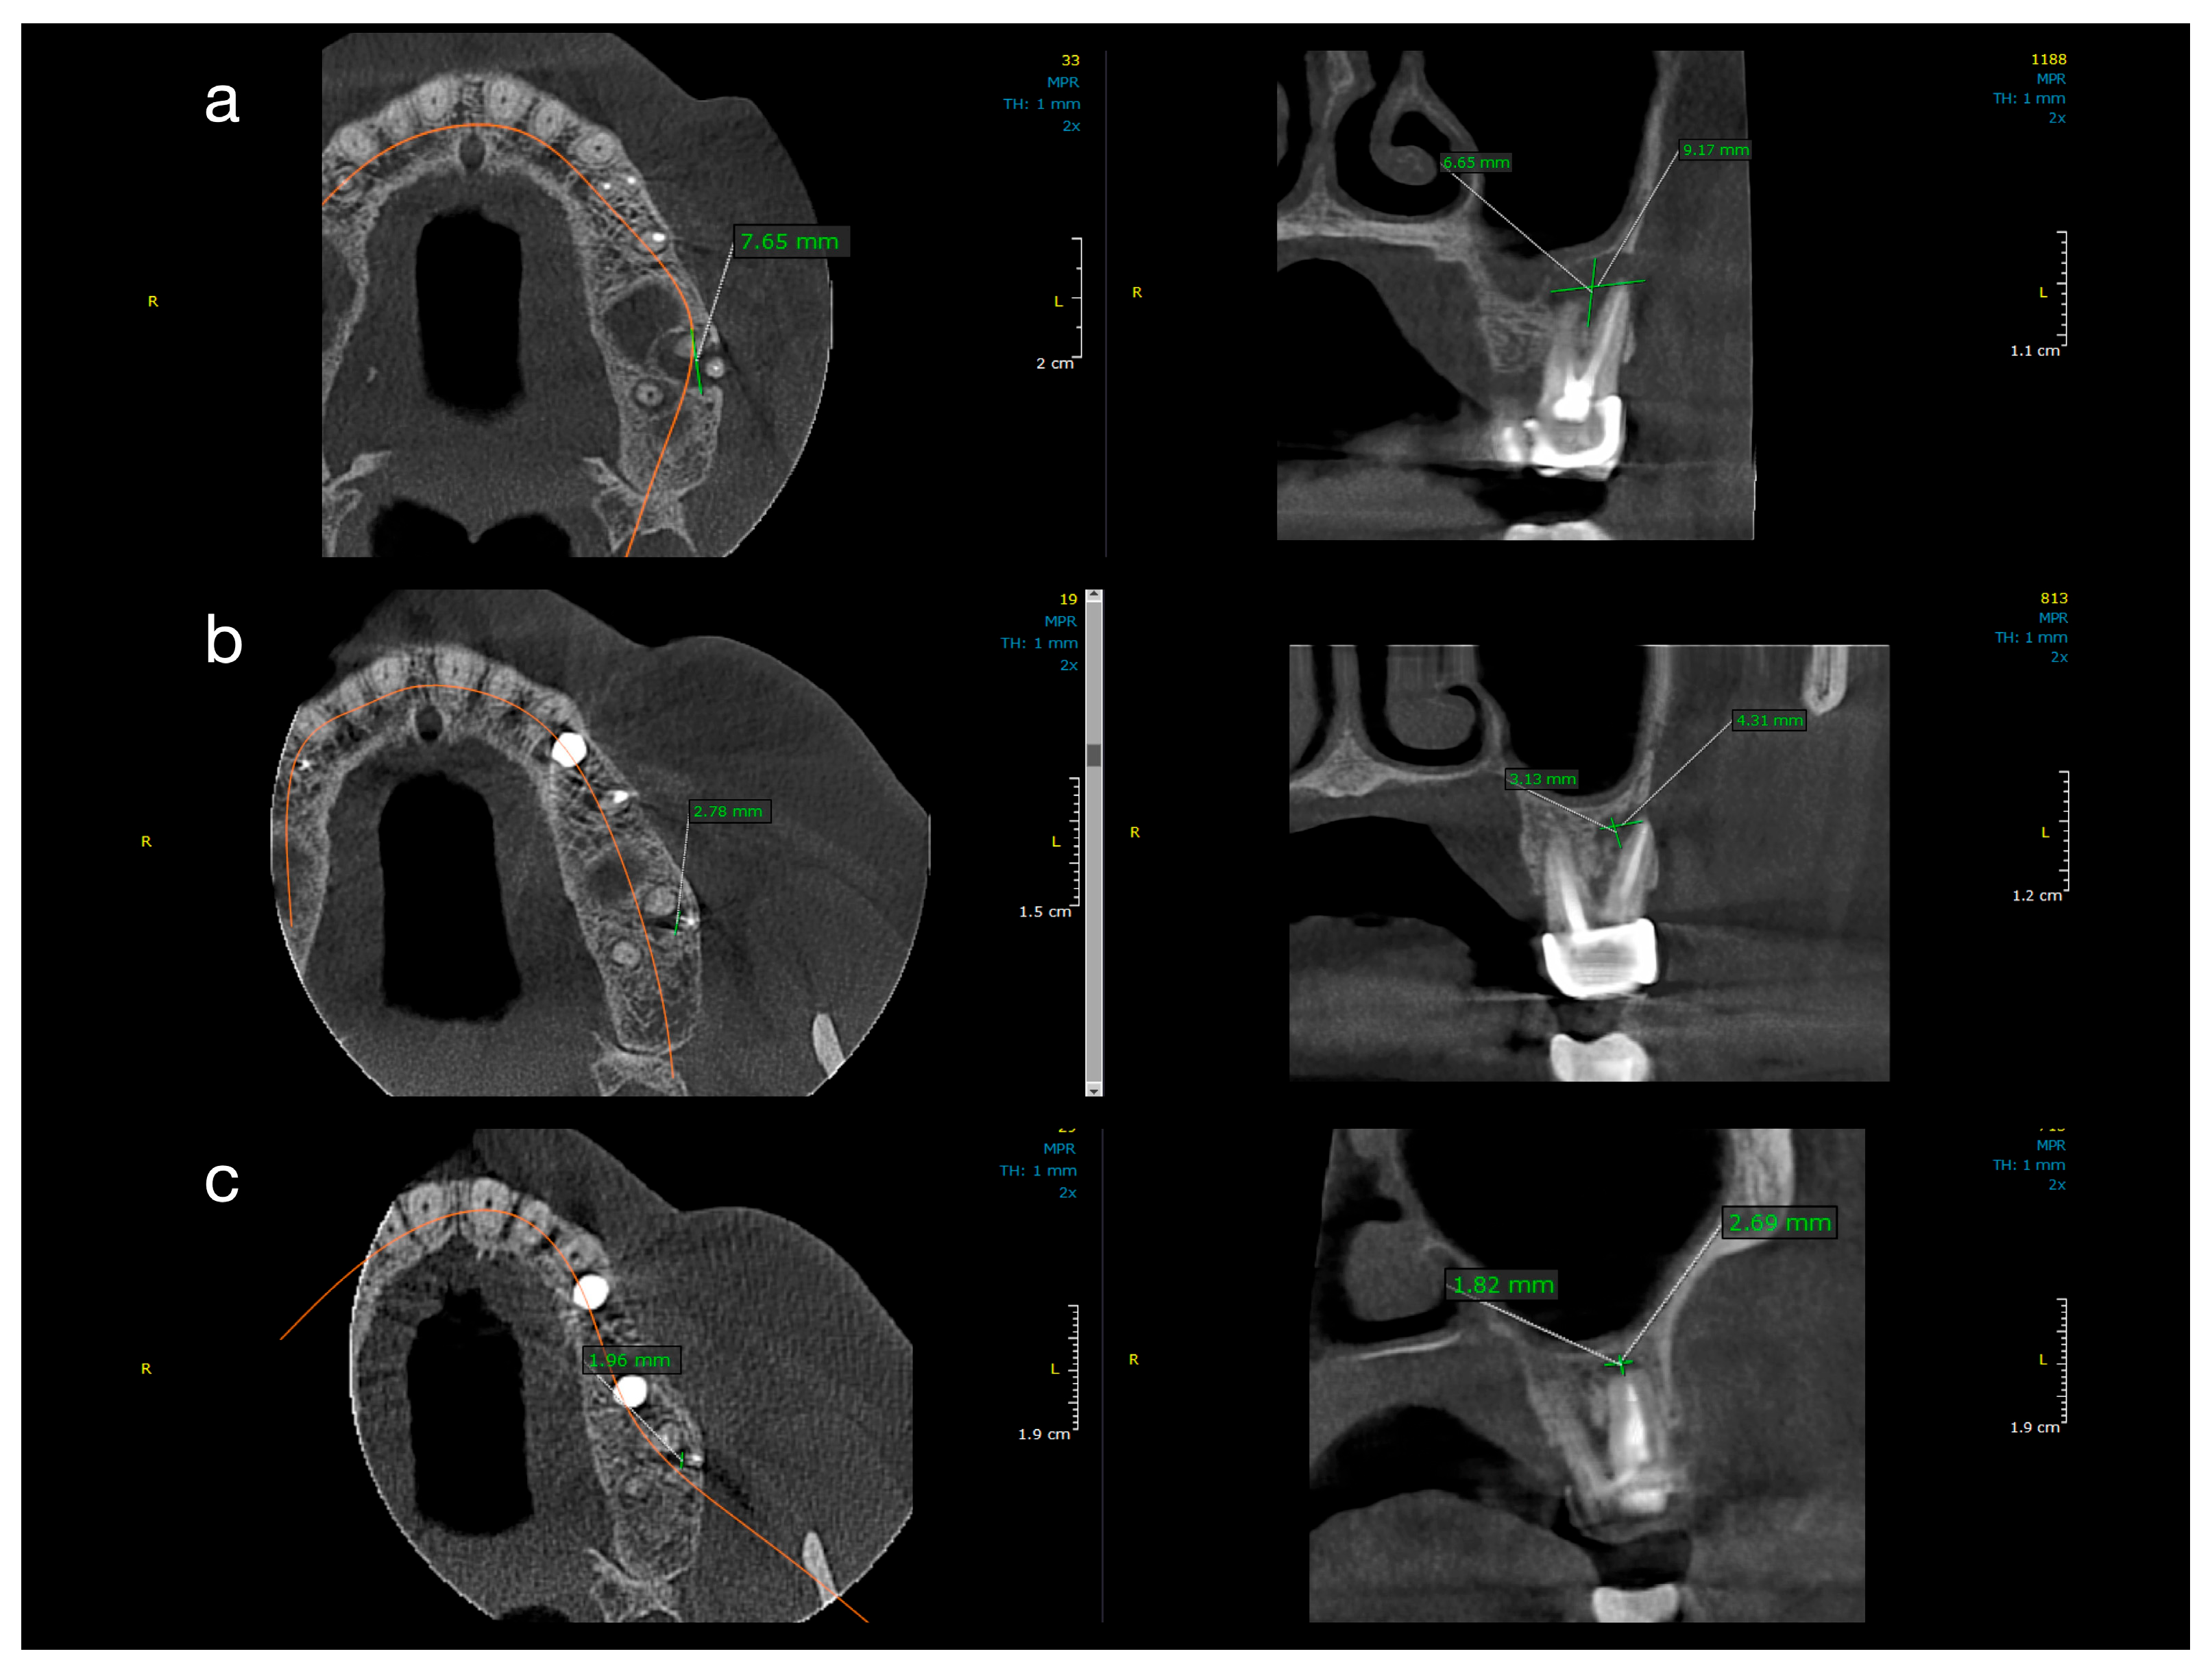

Figure 2. Sequential CBCT images of a case from Group 1 (conventional treatment). Axial, sagittal, and coronal CBCT slices showing lesion reduction in a patient treated with conventional root canal therapy and calcium hydroxide. (a) Baseline: well-defined radiolucency measuring 7.65 mm mesiodistally, 6.55 mm buccolingually, and 9.17 mm vertically. (b) One-year follow-up: partial healing with reduction to 2.78 mm (MD), 3.13 mm (BL), and 4.3 mm (V). (c) Two-year follow-up: near-complete resolution (1.96 mm MD, 1.82 mm BL, 2.69 mm V).

Figure 2 and Figure 3 illustrate representative cases from each group, highlighting the volumetric healing over time. In a Group 1 case (conventional treatment only), the initial lesion (~8–10 mm in diameter in each dimension) showed substantial shrinkage by the 1-year follow-up and almost complete radiological resolution by 2 years. By contrast, a Group 2 case (with decompression), which began with a larger cystic lesion (over 12 mm in its greatest dimension), demonstrated a dramatic reduction in lesion size after 12 months of decompression and continued healing at 24 months, leaving only a small residual radiolucency. These examples underscore the progressive radiographic healing observed in both treatment protocols.

All ten treated teeth remained asymptomatic throughout the follow-up, and sequential CBCT evaluations confirmed continuous lesion regression in every case. Table 1 and Table 2 detail the lesion size measurements (in mm) for each patient at baseline, 1 year, and 2 years in Group 1 and Group 2, respectively. Many lesions exhibited complete or near-complete radiological healing by the end of the observation period (recorded as 0.00 mm lesion diameter in at least one dimension for several cases in both groups). At baseline, Group 2 lesions were notably larger than those in Group 1. The mean initial lesion diameter in Group 2 was 13.7 mm (±3.34), compared to 7.3 mm (±1.74) in Group 1 (Table 3). This difference was statistically significant (p < 0.001), confirming that Group 2 started with more extensive periapical lesions. It is noteworthy that the baseline lesion size data in both groups showed no significant departures from normal distribution (see Table 4 for normality test results), which validated the use of parametric statistical comparisons.

By the 12-month follow-up, the lesion dimensions had decreased markedly in both groups (Table 3). In Group 1 (standard endodontic therapy), the mean lesion diameter reduced from 7.3 mm at baseline to 2.93 mm (±0.75) at one year. In Group 2 (endodontic therapy + decompression), the mean lesion diameter decreased from 13.7 mm to 5.21 mm (±4.75) at one year. Although the lesions in Group 2 remained larger in absolute terms after 12 months, the difference between the two groups was no longer statistically significant (p = 0.087). Figure 4 presents violin plots of the lesion size distributions at baseline and one year, illustrating the substantial shift toward smaller lesion diameters in both cohorts. The spread of the violin plot for Group 2 at one year was broader, reflecting greater variability in healing outcomes among those larger initial lesions. By the 24-month follow-up, both groups showed further improvement. Group 1 lesions had a mean diameter of 1.12 mm (±0.98), and Group 2 lesions averaged 2.41 mm (±5.15). This slight residual difference was not statistically significant (p = 0.356). Radiographically, most lesions in both groups had resolved or nearly resolved by two years, with only very small radiolucencies, if any, remaining. It was observed that Group 2 continued to exhibit a higher variability in lesion size outcomes at 24 months (as evidenced by a larger standard deviation and wider confidence interval in Table 3). Importantly, within each group, the reduction in lesion size from baseline was highly significant. Both Group 1 and Group 2 demonstrated statistically significant lesion shrinkage at the 1-year and 2-year evaluations compared to baseline (intragroup comparisons, p < 0.001 for all). This confirms that both treatment approaches achieved effective and progressive lesion resolution over time in their respective groups.